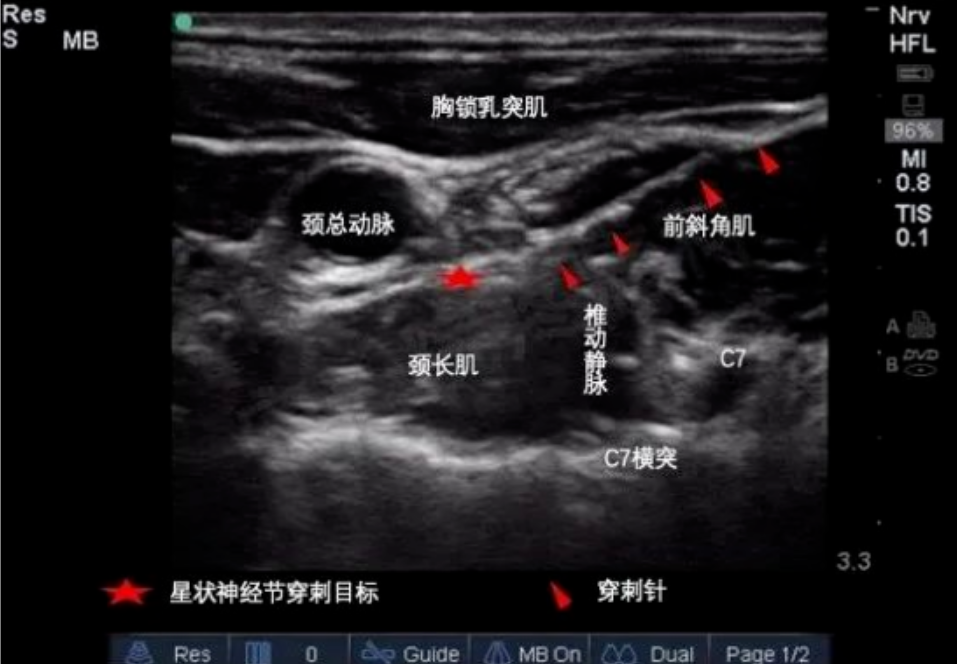

1. 星状神经节阻滞(SGB)

原理:通过超声引导将局麻药精准注射至颈部星状神经节,调节交感神经张力,恢复自主神经平衡,改善脑血流和内分泌功能;

适应症:顽固性失眠、偏头痛、植物神经功能紊乱、焦虑抑郁相关睡眠障碍;

优势:安全性高(超声可视化操作),疗效显著(多数患者1-2疗程后睡眠质量提升)。